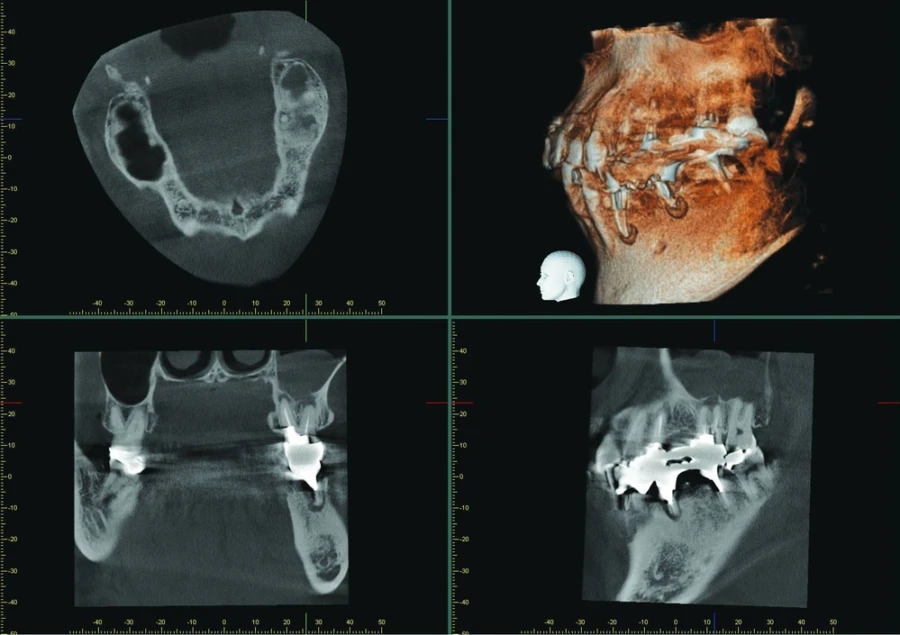

Đọc tiếpImages taken with Veraviewepocs 3D R100 The patient presented with an unclear situation around tooth 26, which had undergone endodontic…